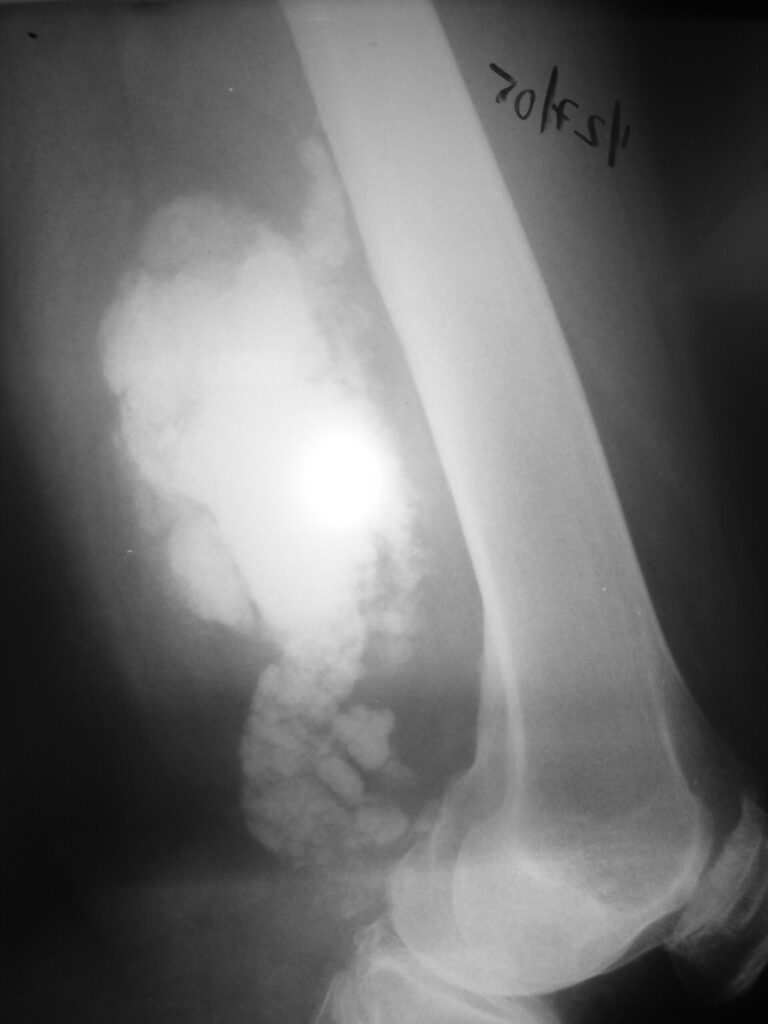

On radiographs, extraskeletal osteosarcomas show a mass with soft tissue density and variable amounts of mineralization best visualize on an Xray or CT scan, which may appear as a dense, cloudlike area (Fig. 1-3). A well circumscribe heterogeneous mass, Isointense to muscle on T1-weighted images and isointense to mildly hyperintense on T2-weighted images (Fig. 4-7). Mineralized areas will be dark on T1 and T2 weighted images.

Fig. 1 & 2: Plain x-rays of the distal femur showing an extraskeletal osteosarcoma. AP (Fig. 1) and Lateral (Fig. 2) views show a soft tissue density with intense mineralization in the posterior thigh. Mass is not originating from the bone.